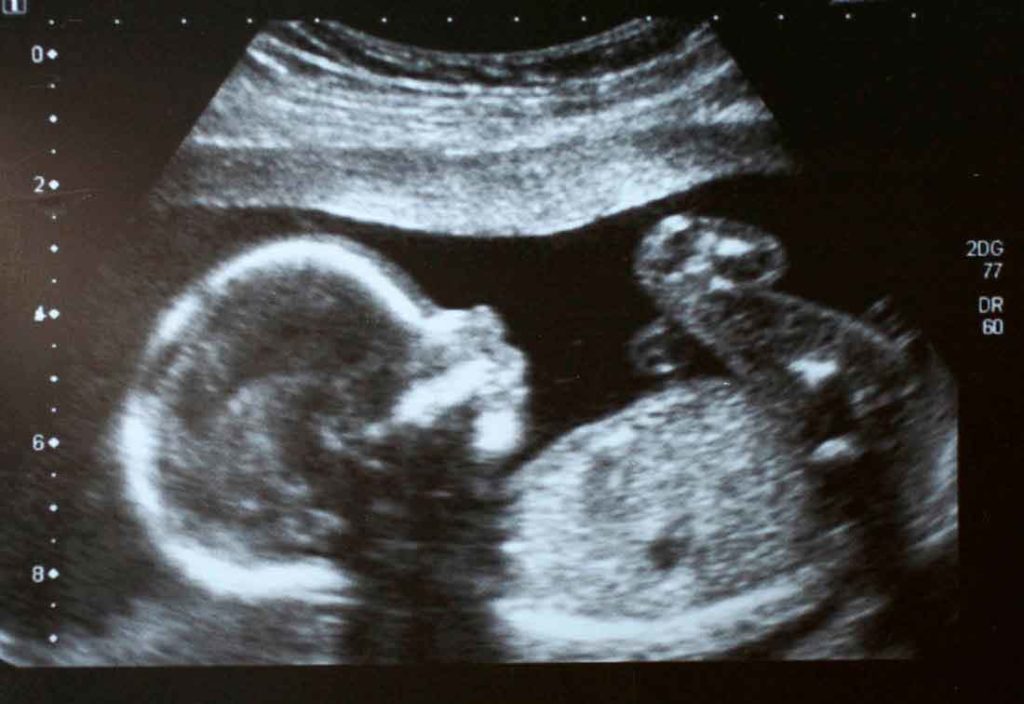

Ultrasound, also referred to as sonography, is a non-invasive technique used to capture internal images of the body, including blood vessels, muscles, organs and other soft tissues. Ultrasounds may be performed to monitor the progress of a growing fetus inside a mother’s uterus, to detect abnormalities or signs of disease or even to visually assist with surgeries and biopsies.

The transducer is passed over the area of the body that covers the internal structures to be imaged. It is the transducer that emits sound waves at frequencies ranging between 1 and 10 MHz (megahertz). In turn, the sound waves are reflected back to the transducer after they bounce off the structures that are the focus of the ultrasound. The central processing unit measures the echo intensities and speed. These measures are converted into electronic images that show up on the machine’s monitor.

Just like the continual evolution of computers and personal communication devices, ultrasound technology continues to advance. Originally, ultrasound technology only presented one- and two-dimensional pictures. Now there are machines capable of generating three-dimensional images. The first three-dimensional ultrasound machine dates back to the mid 1980s; Kazunori Baba, at the University of Tokyo used this innovative technology to capture 3D images of a fetus. There are even four dimensional ultrasound machines now which generate 3D scans in real time.